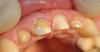

ходок Опубликовано 5 октября, 2013 Поделиться Опубликовано 5 октября, 2013 Дорогие друзья! Решил поделиться работой. Хочу начать как обычно с опроса. Выкладываю фото фронта. Кто как видит - мужчина или женщина пациент и кто сколько видит реставраций? Завтра публикую остальные фото. 1 Ссылка на комментарий

ходок Опубликовано 6 октября, 2013 Автор Поделиться Опубликовано 6 октября, 2013 Дц с нанесением e-max 12,11,21,22. 24 - старая МК 4 Ссылка на комментарий

ходок Опубликовано 6 октября, 2013 Автор Поделиться Опубликовано 6 октября, 2013 (изменено) Милая работа. Из каких соображений выбрали дц?Стася, наверное помнишь тему "контрольный в голову" от меня полгода назад и модели из алебастра. Эту работу делал другой техник. Фото его модели прикрепляю. Человек хочет и любит работать. Выбрал из соображений мат-технической базы (сказал технику что надо приобрести пресс и делать единички на прессе хотя бы из соображений адгезии). Думаю, решится и это. вот еще прикус у девушки Изменено 6 октября, 2013 пользователем ходок 2 Ссылка на комментарий